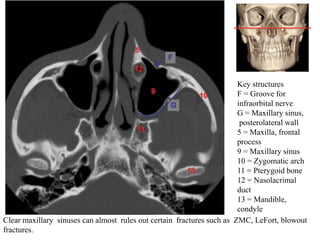

Key structures

F = Groove for

infraorbital nerve

G = Maxillary sinus,

posterolateral wall

5 = Maxilla, frontal

process

9 = Maxillary sinus

10 = Zygomatic arch

11 = Pterygoid bone

12 = Nasolacrimal

duct

13 = Mandible,

condyle

Clear maxillary sinuses can almost rules out certain fractures such as ZMC, LeFort, blowout

fractures.